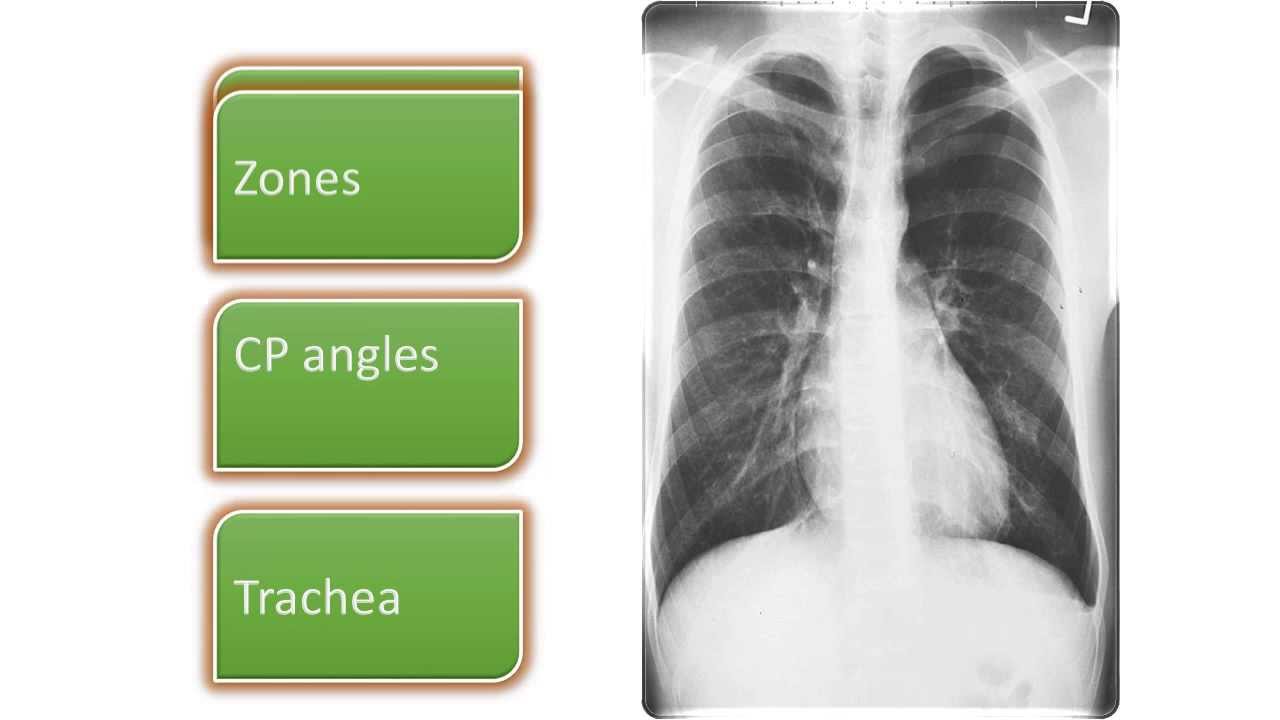

From www.slideserve.com

PPT Chest Radiography LECTURE.2 PowerPoint Presentation, free Chest X Ray Lecture — a description of a systematic method for examining a chest x. a free medical lecture on chest x ray (cxr) interpretation. In fact every radiologst should be an. Understand the key concepts of reading a chest radiograph with this. Chest X Ray Lecture.